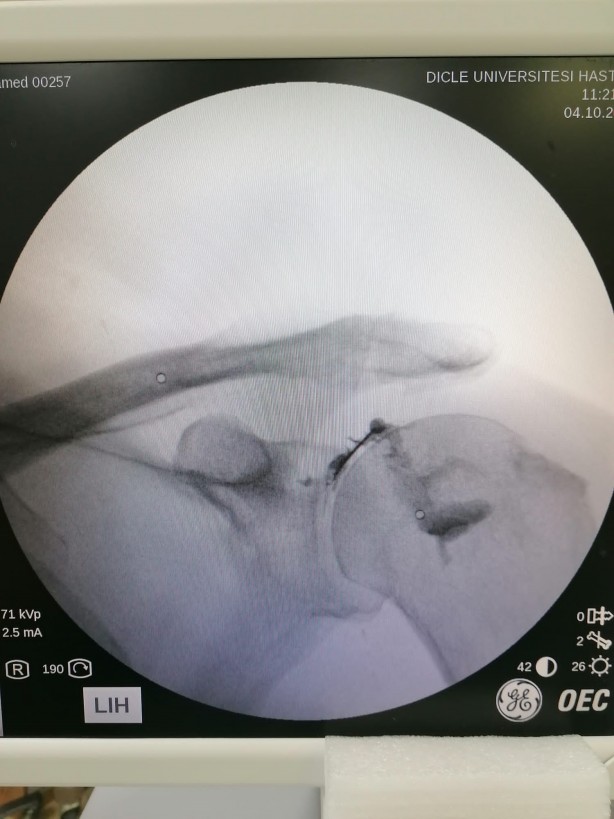

Kök tedavisinin görüntüleme eşliğinde yapılması gerektiğine dikkat çeken Karaman, şunları kaydetti: “Kök hücre tedavisi, körlemesine yapılan bir tedavi değildir. Mutlaka görüntüleme eşliğinde yapılıyor. Hastamıza tedavi uygularken floroskop cihazını kullanmaktayız. Uygulama anına geldiğimiz zaman hastanın ilgili bölgesinin tam olarak görüntüsünü görmekteyiz. Burada birebir koordineli bir şekilde özel iğne şeklinde olan elektrodumuz var. Onunla beraber ekrandan göre göre ilerletiyoruz. Daha sonra doğrulamak için yerimizi boya veriyoruz. Dağılımı gördükten sonra hastamıza kök hücreyi verip işlemimizi tamamlamış oluyoruz.”